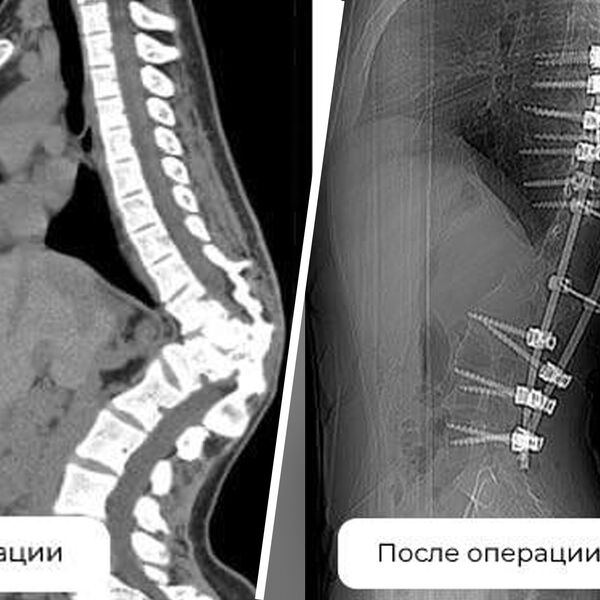

Девушке был диагностирован кифосколиоз — S-образное искривление позвоночника с образованием задней выпуклости в грудном отделе. На фоне врожденной патологии — неправильно сформированного позвонка — у нее развился сколиоз 72 градуса и вырос горб.

Чтобы помочь девушке, медики провели три операции. Во время первой ей установили аппарат внешней фиксации, во время второй — удалили деформированный позвонок в грудном отделе и сделали дополнительную коррекцию. В ходе третьего вмешательства позвоночник пациентки зафиксировали внутренней конструкцией.